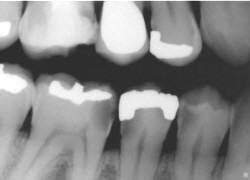

La información

radiográfica contribuye significativamente a los hallazgos

clínicos en términos del hallazgo de lesiones en diferentes

estadíos de progresión (29,32)

Las radiografías ayudan a estimar la profundidad de

desmineralización por caries en el esmalte y la dentina. La

profundidad no siempre está asociada con la presencia de

cavidad de caries, en especial en superficies proximales.

Investigaciones

clínicas que se realizaron en un país con una tasa baja de

progresión de caries revelaron que, en promedio, el 32% de

las lesiones visibles radiográficamente que se extendían

hasta el tercio externo de la dentina no había cavidad de

caries; por el contario, el 72% de las lesiones que se

extendían hasta 2/3 partes de la dentina tenían cavidad de

caries (33) Las

lesiones con cavidad de caries clínicamente o las lesiones

con obvia radiolucidez en dentina (más profunda que el 1/3

externo) en la superficie oclusal están altamente infectada

la dentina, debajo de la unión amelo-dentinaria (34,35)

Si las radiografías están disponibles, el

primer paso es clasificar las lesiones de caries coronal en

dientes posteriores de acuerdo con los grados que están en

la Tabla 4.